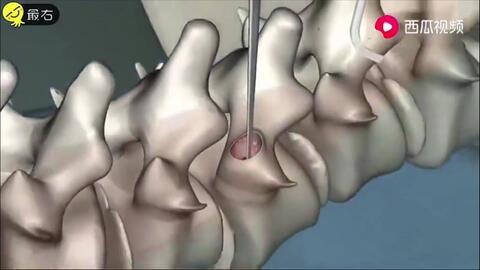

脊柱矫正的原理其实很简单,就是通过外力来改变脊柱的受力点,从而逐步调整脊柱的形态。这个过程需要耐心和毅力,因为脊柱矫正并非一蹴而就的事情。

4. 手术:对于一些严重的脊柱弯曲,可能需要通过手术来矫正。手术方法包括脊柱融合术、脊柱截骨术等,但手术风险较大,需要在专业医生的指导下进行。